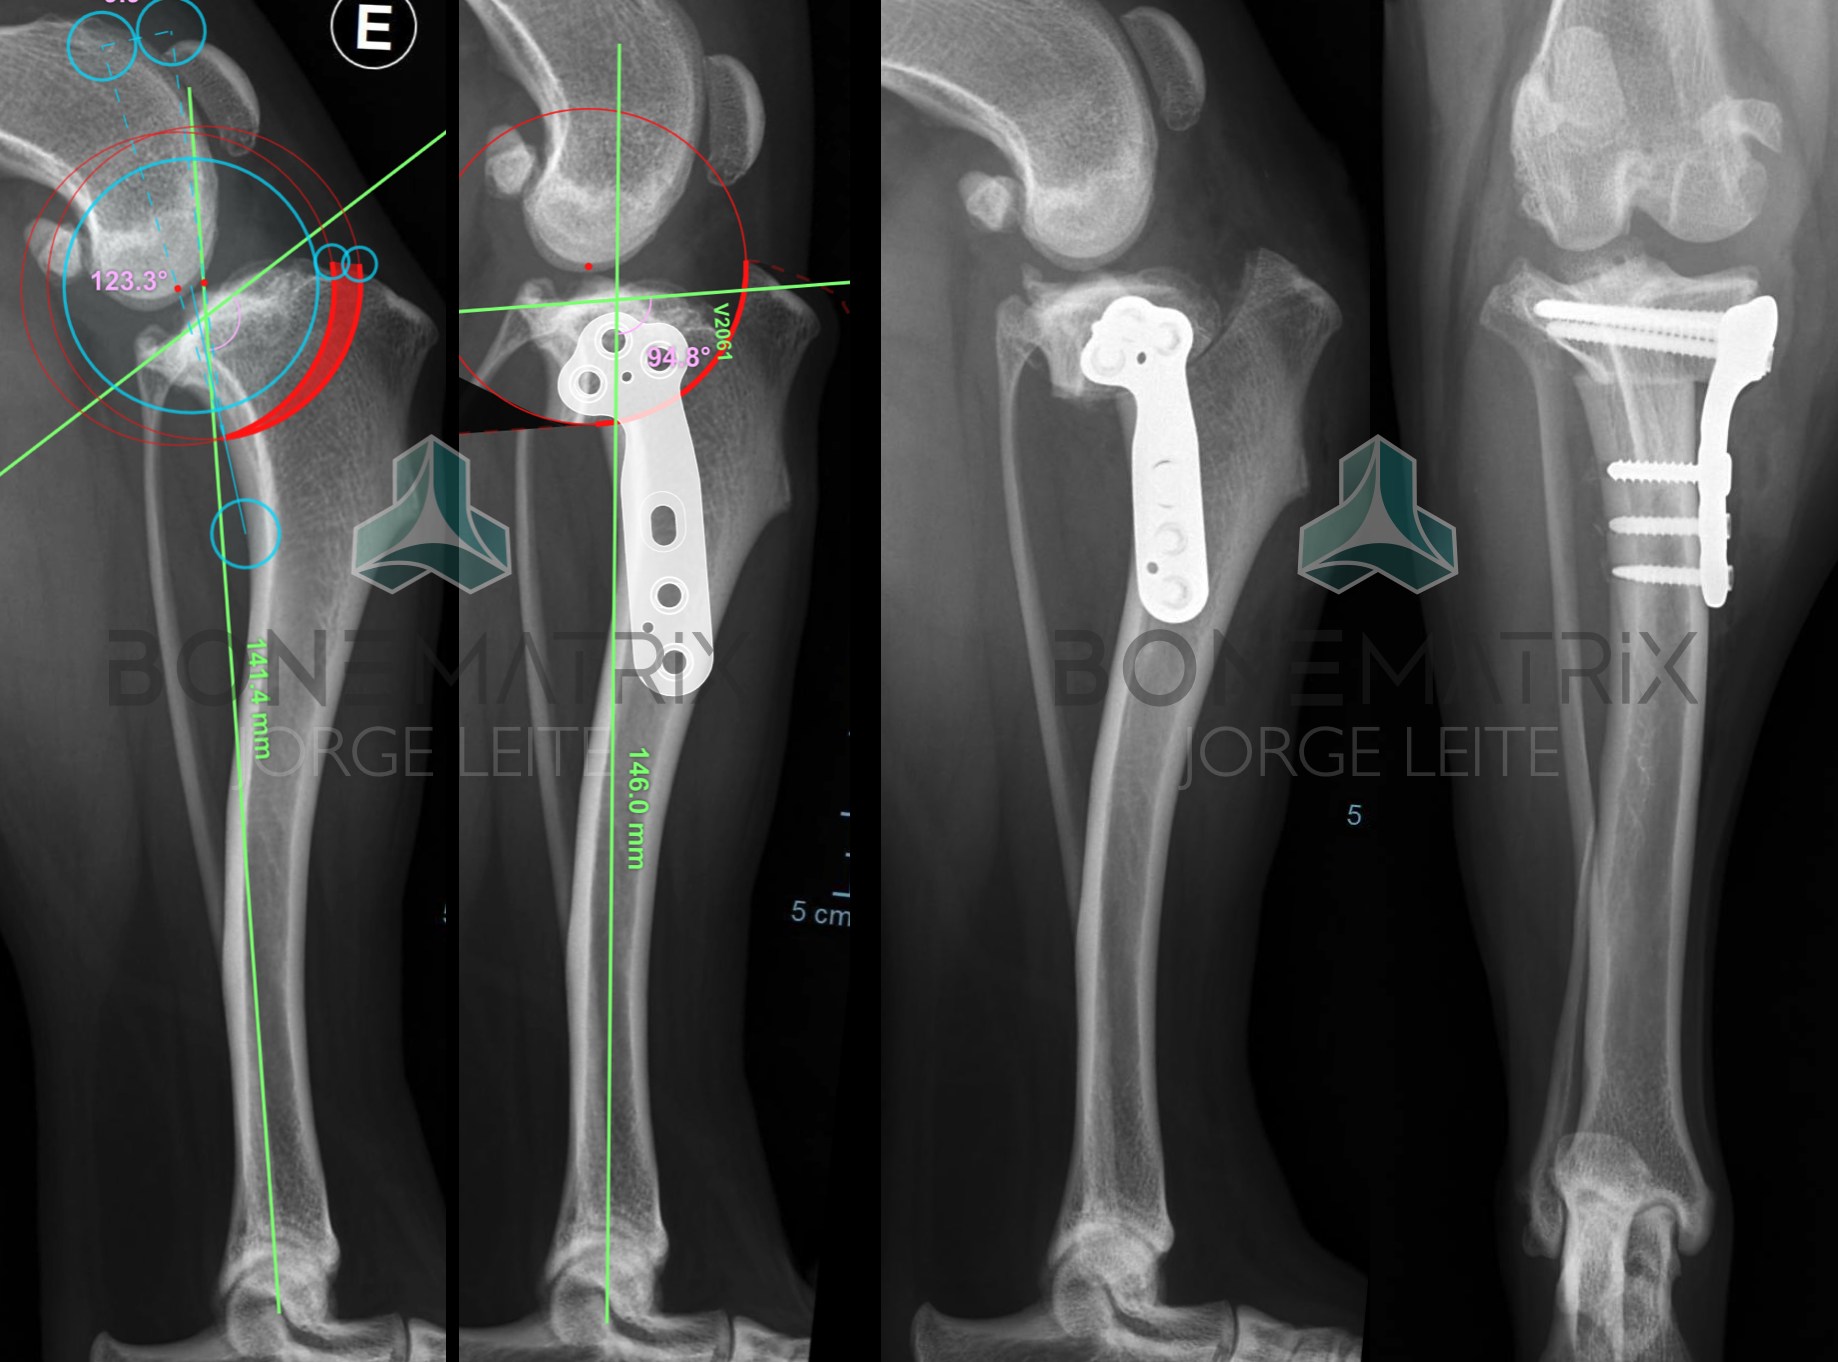

Compartimos dos ejemplos con casos de hoy en los que se usaron dos soluciones diferentes para estabilizar rodillas con alto TPA.

En el primero, el uso de una placa L FIXIN (V2007) que permite estabilizar un fragmento de forma segura, a pesar del alto efecto contrarreloj que aparece tras la rotación.

En la segunda rodilla, el uso de un TPLO "doble corte", para obtener una corrección adecuada, con una menor rotación. En este segundo caso se utilizó una placa Clover Fixin V2063.